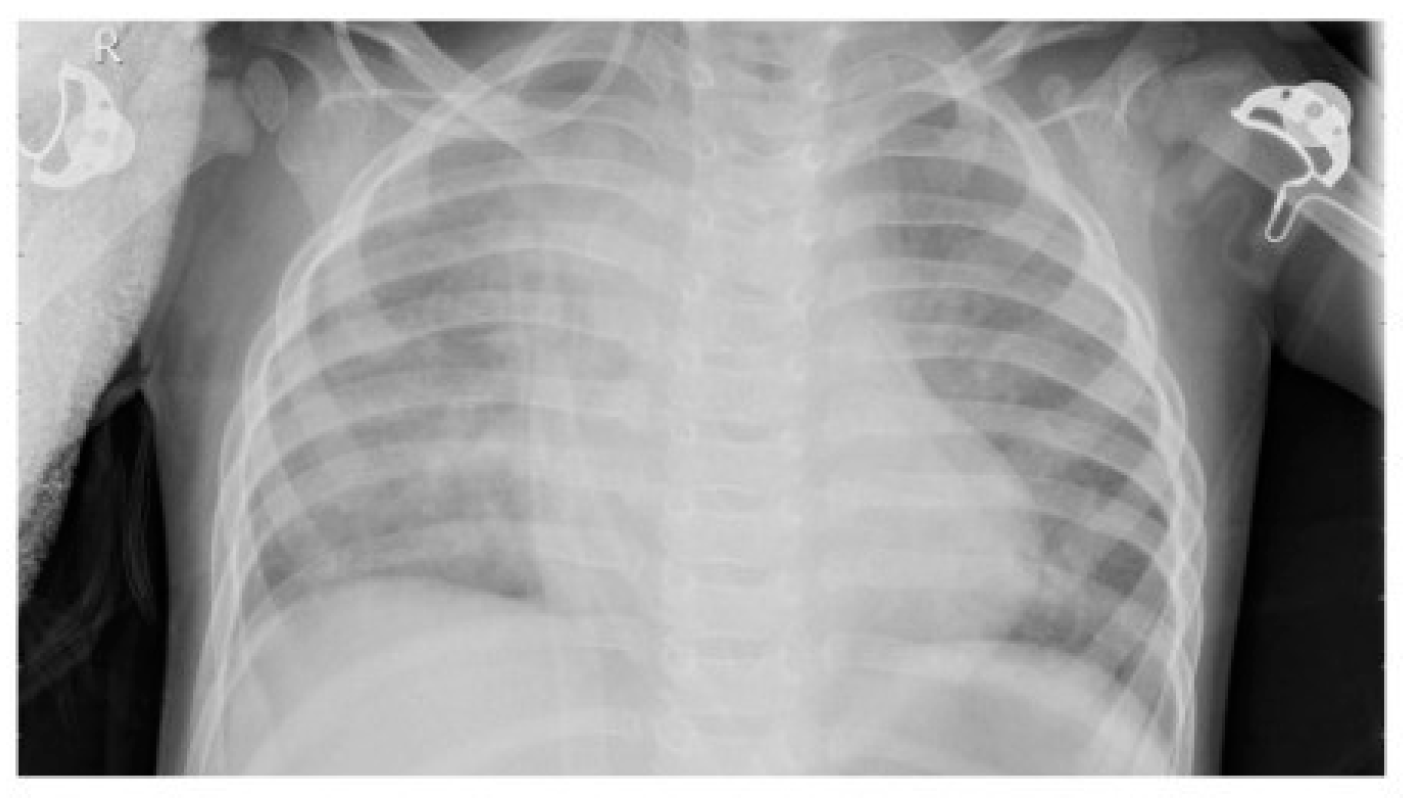

2.2. Dataset

2.4. Image Enhancement Techniques

Resizing

2.5. Normalization